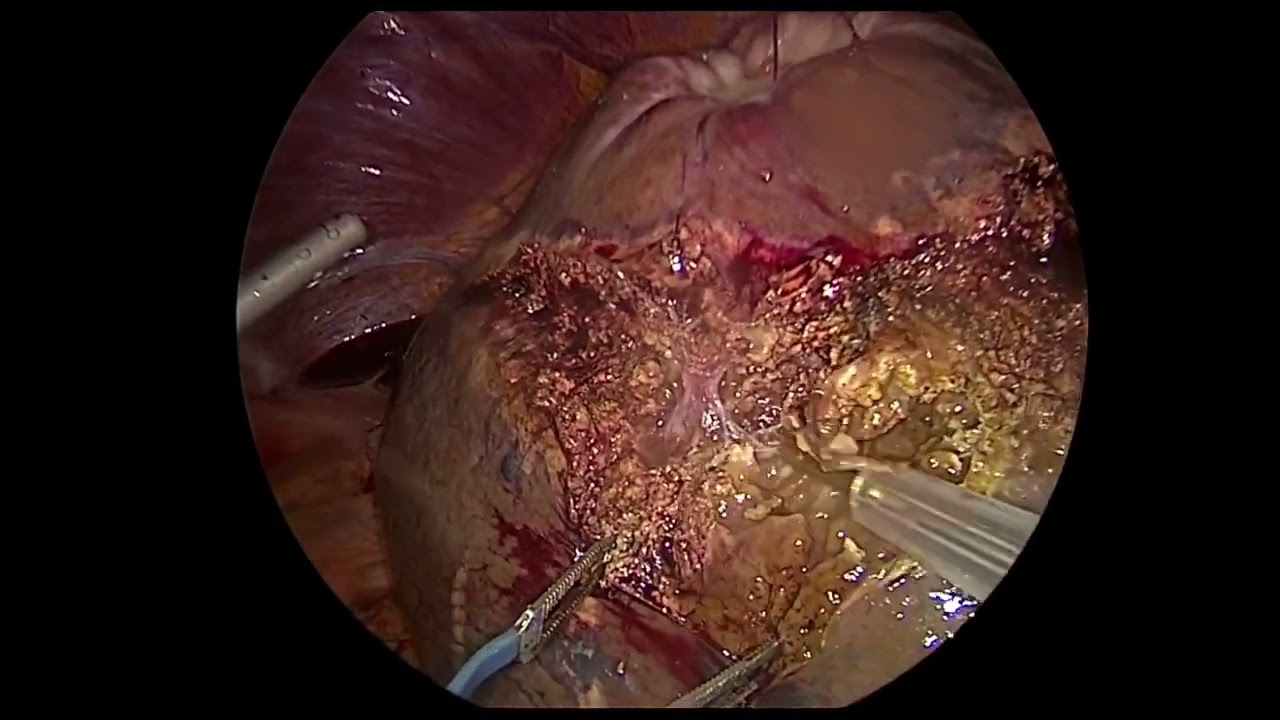

LAPAROSCOPIC ANATOMICAL SEGMENT 8 RESECTION WITH CRANIAL APPROACH